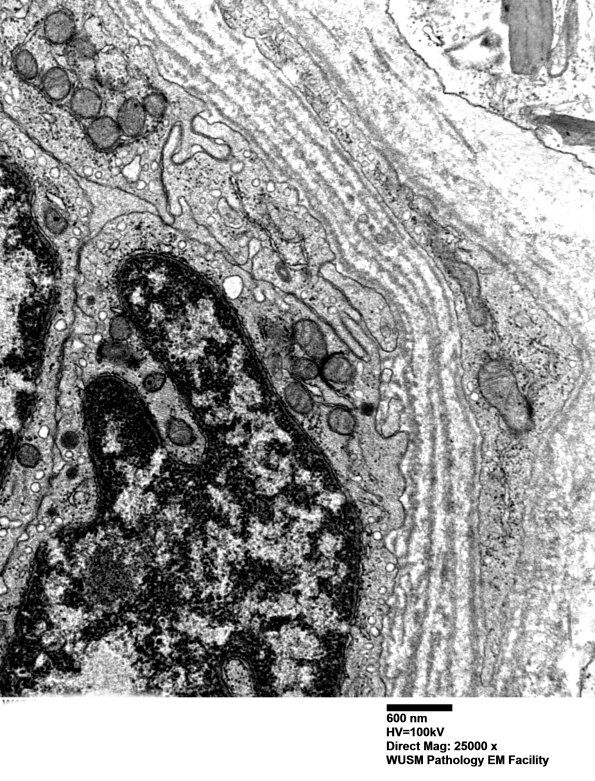

Washington University Experience | VASCULAR | Hypoxia-Ischemia, fetal-neonatal | White Matter | 16B6 (Case 16) HIEM EM029 - Copy

16B6 (Case 16) HIEM EM029 - Copy